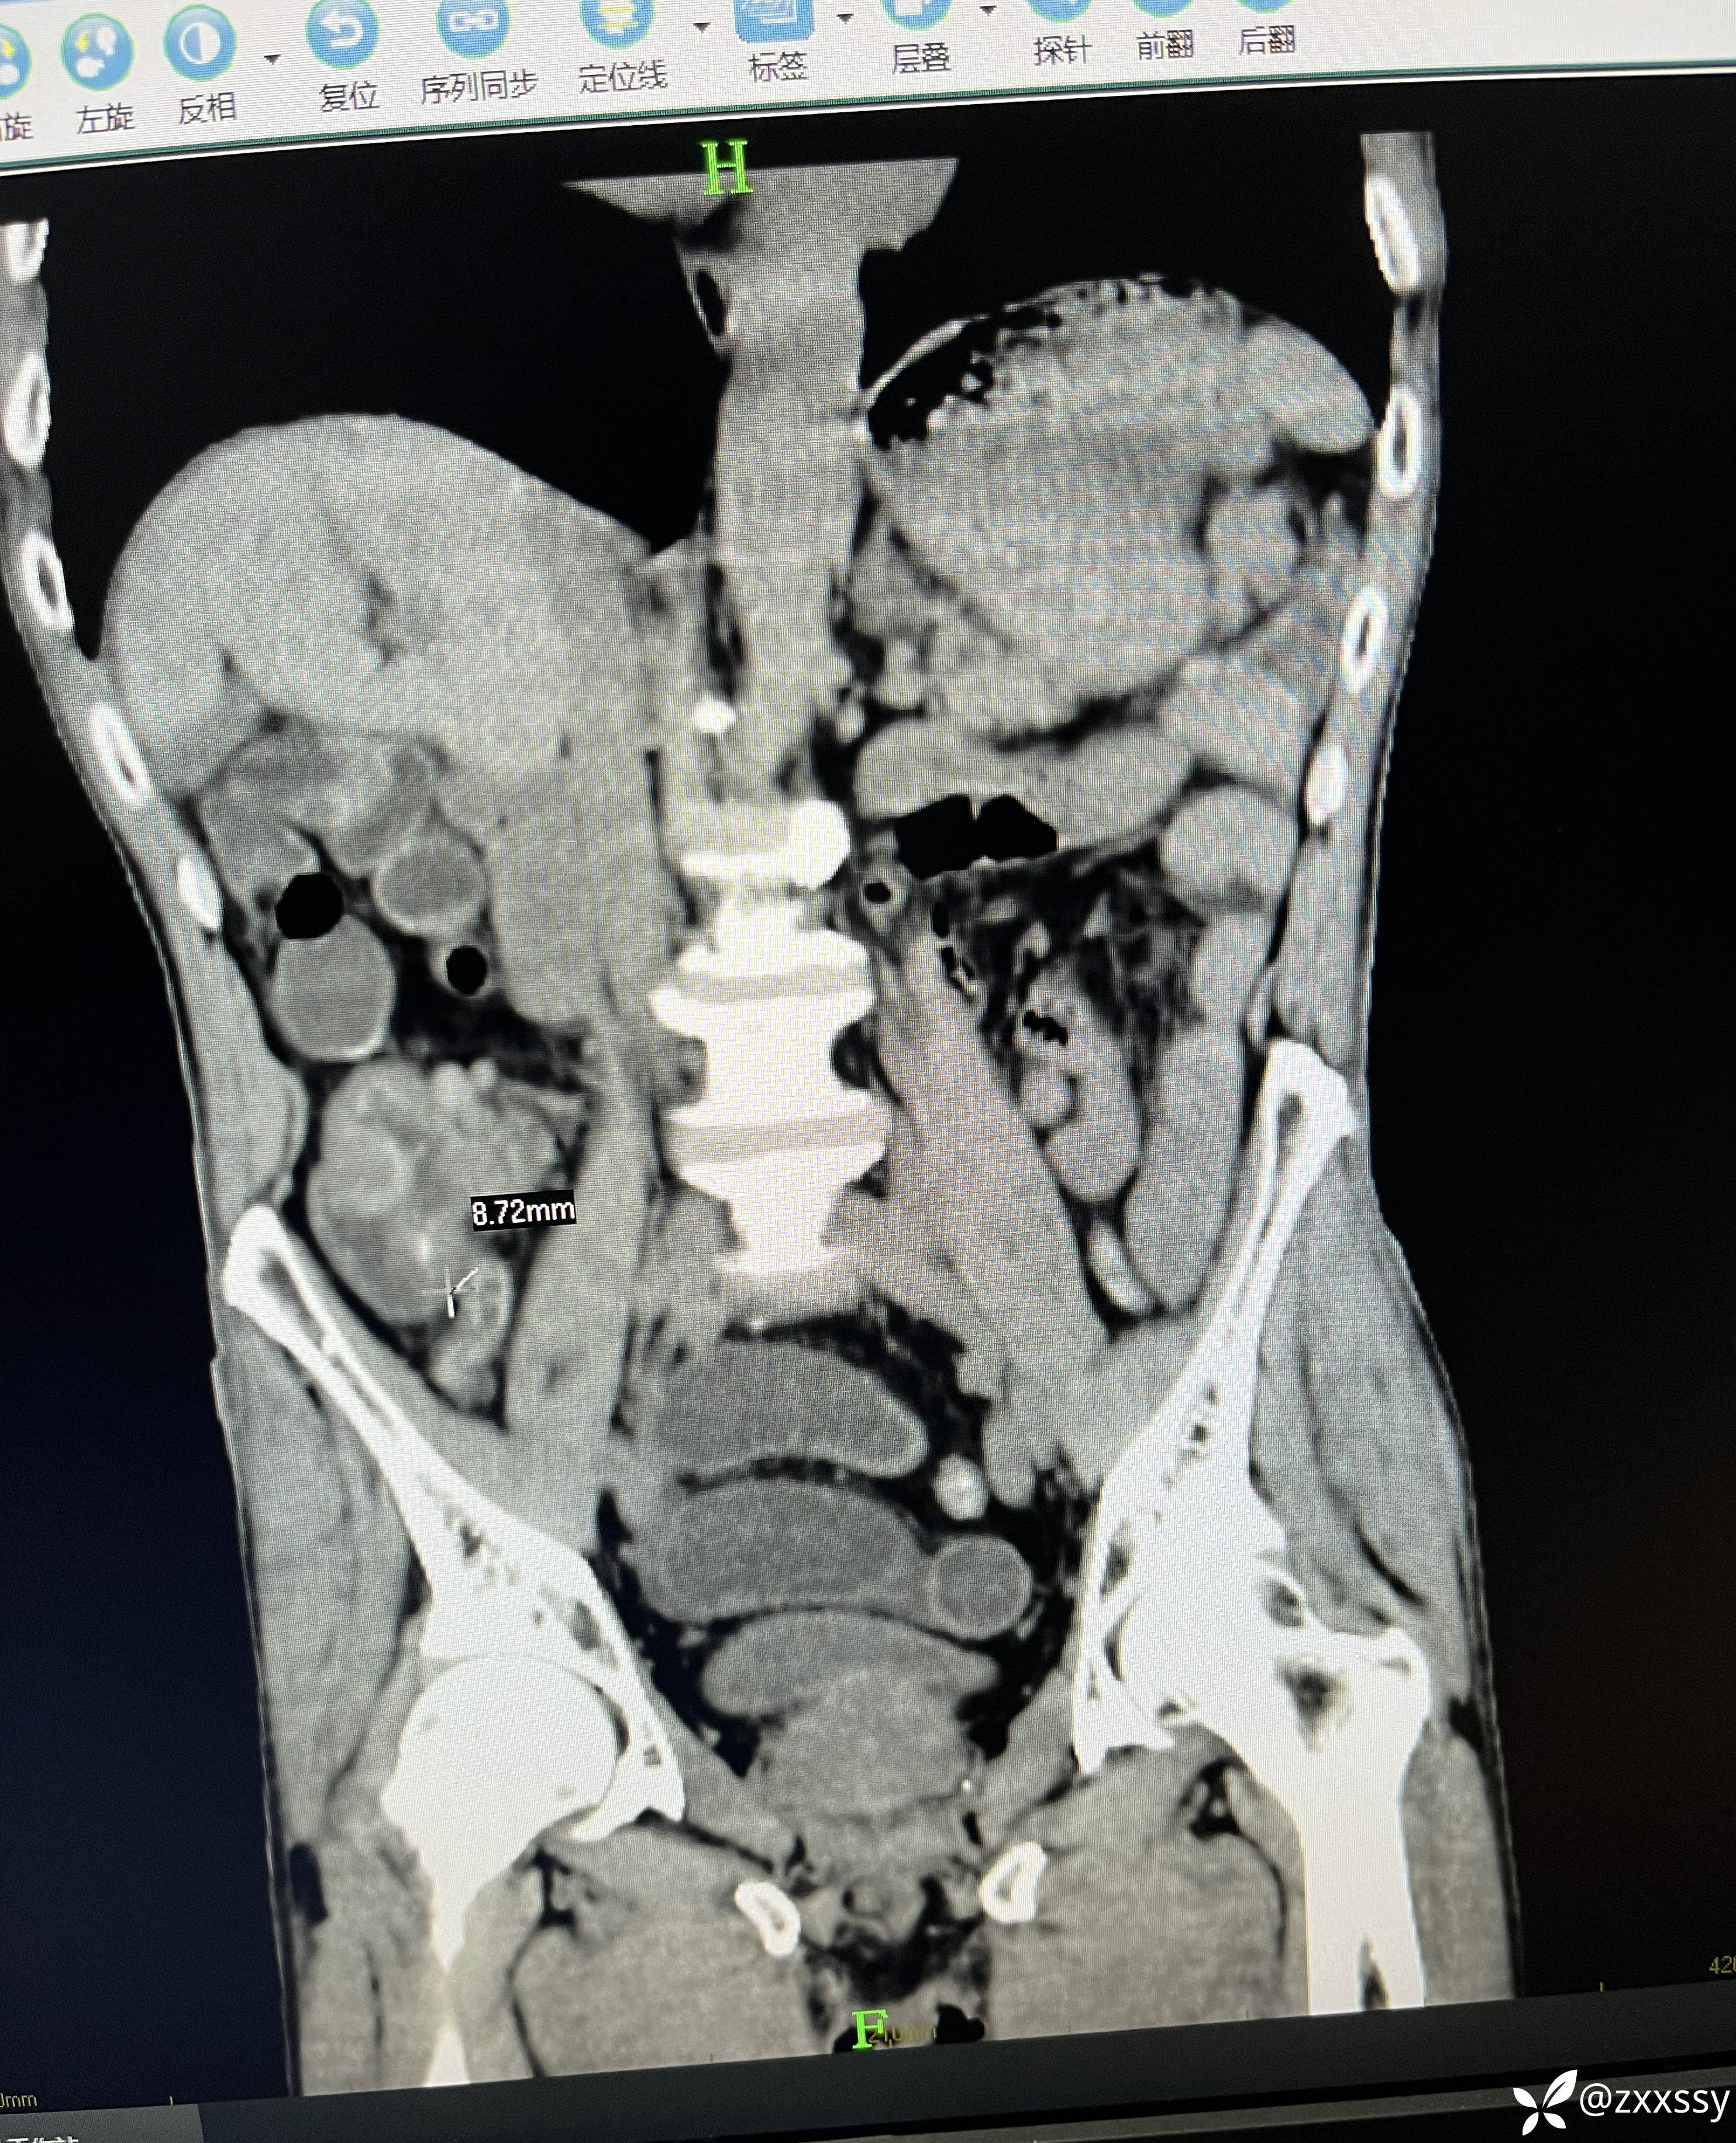

临床诊断:1.急性阑尾炎并粪石形成;2.小肠梗阻;3,回盲部管璧不规则增后,周围淋巴结多发(回盲部肿瘤?);4.盆腹腔积液。

更踪和术者交流:回盲部肿瘤合并急性阑尾炎,术前影像检查已经发现有回盲部肠壁增厚了,但是阑尾的炎症同样很明显,术中可见回盲部明显质硬包块,将回盲部肠壁向内牵拉,形成明显的环形带,但尚未造成明显肠梗阻!考虑到患者已经70岁的年纪,如果要做右半结肠切除的话是完全可以做的,但是手术风险会高很多,于是在跟家属沟通交流、跟手术组人员讨论后决定暂不行肿瘤根治术,待本次手术后患者机体康复到一定程度再进行肿瘤根治术!